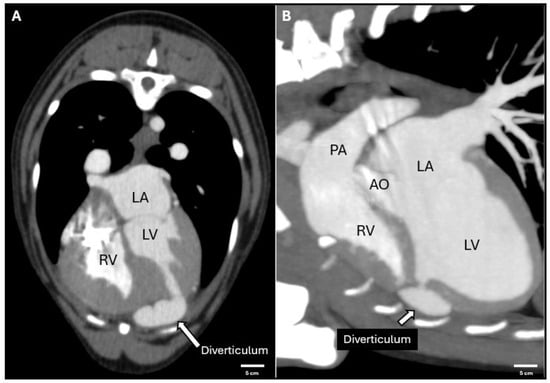

4. Cardiac Synchronous Computed Tomography